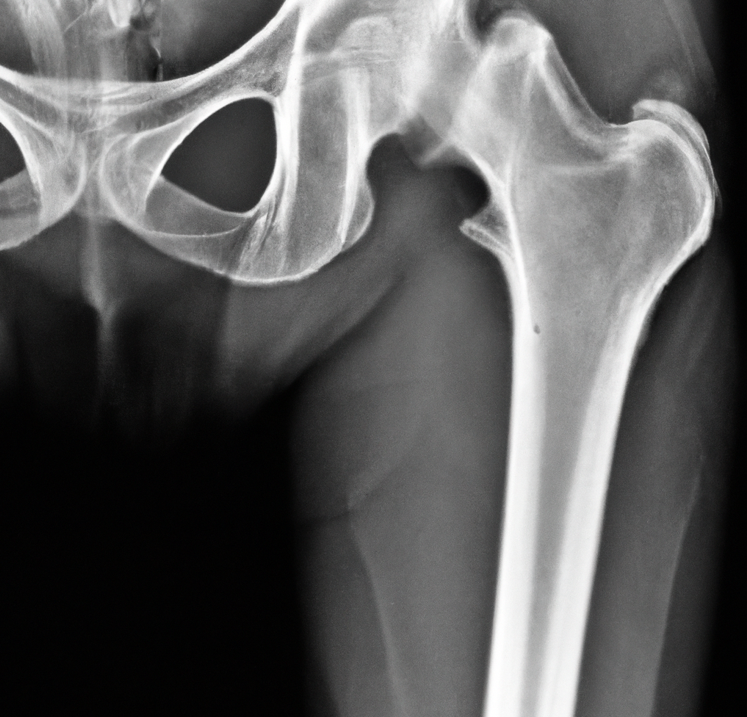

골다공증을 예방하고 관리하기 위해 규칙적이고 몸에 맞는 적절한 운동요법이 매우 중요합니다. 다음은 골다공증에 도움 되는 운동 요법 몇 가지입니다.